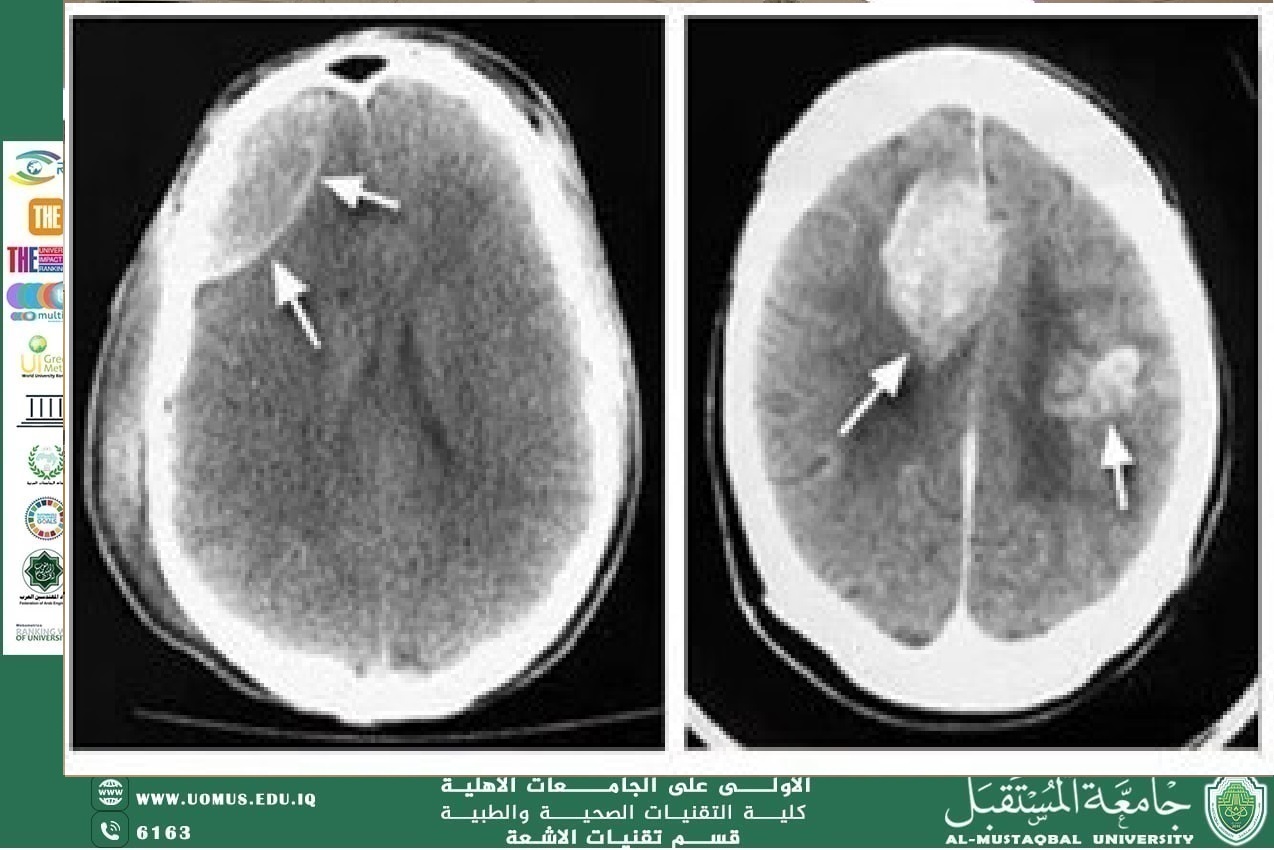

The Role of CT in Detecting Tumors

Early diagnosis: Enables detection of tumors even in their initial stages.

Determining tumor location and size: Assists surgeons in planning accurate surgical interventions.

Monitoring treatment response: For example, evaluating tumor size after chemotherapy or radiotherapy.

Tumor differentiation: When combined with other techniques such as PET-CT, it can distinguish between benign and malignant tumors.